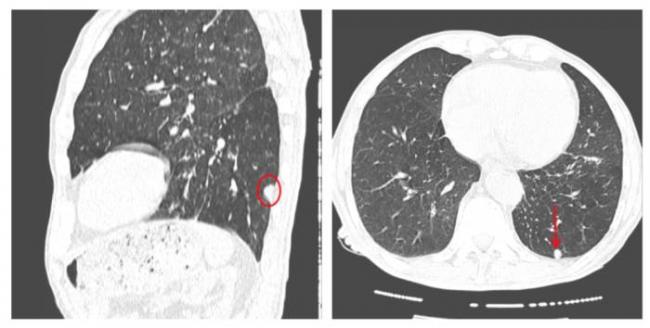

Как очаги в легких выглядят на снимке КТ?

Чтобы человек несведущий смог разобраться в результатах КТ, следует знать о нюансах чтения снимков. Рассмотрим самые актуальные:

- Очаговые образования представляют собой участки белого цвета на черном фоне (на снимке-негативе). В реальности пораженная область, скорее всего, имеет более темный цвет, чем здоровые ткани легкого.

- Если врач заметит на снимке участки кальцинирования или обызвествления (капсул, пропитанных солями кальция) вокруг очага, это может быть признаком доброкачественности образования. Кальцинаты по цвету похожи на кости скелета, видимые на этом снимке. Такие явления часто обнаруживаются после затяжных простудных заболеваний, бронхитов или уже излечененного туберкулеза и представляют собой некий шрам на легких. Пациента с образованием, на котором заметны признаки кальцината, пульмонологи обычно просят раз в полгода делать контрольные снимки.

- В случае, когда образование представляет собой так называемое «облачко» или очаг по типу «матового стекла», требуется более предметное обследование. Внешне оно выглядит как затуманенная область с размытыми границами. В ряде стран пациентам с такими образованиями сразу рекомендуется операция, даже если оно не растет. Уже доказано, что в 80% случаев такие очаги являются предраковым состоянием легких. Альтернатива немедленной операции — постоянное наблюдение с контрольными снимками раз в полгода-год.